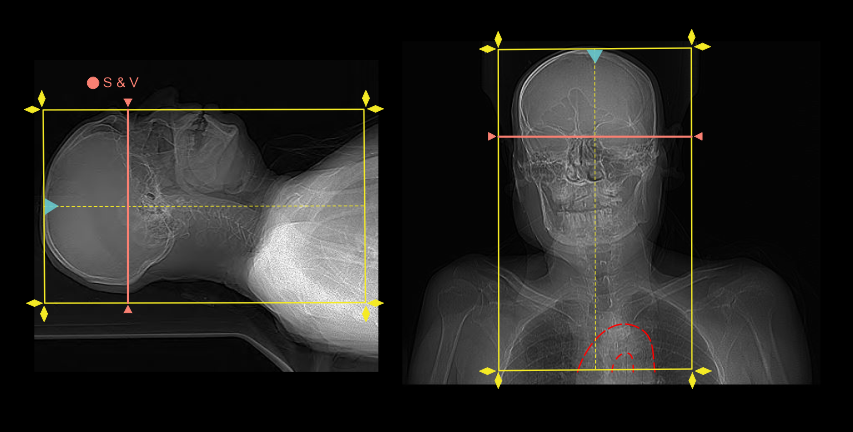

- Plan the scan-and-view (S & V) slab just above the skull base.

Explanation: manual start is used to initiate the scan because it’s quite challenging to find cerebral arteries in the scan-and-view slab (pre-contrast) and also to place a smaller region of interest (ROI).

- Scan direction is planned to initiate from head to foot.

Explanation: avoids delayed acquisition in superior region of the cerebral arteries, visualizing cerebral veins and evades streak artifacts at the root of the neck when there is undiluted contrast media in brachiocephalic and subclavian veins.

- Plan five seconds from contrast media initiation to S & V initiation.

- Plan zero or minimum delay time to start arterial step.